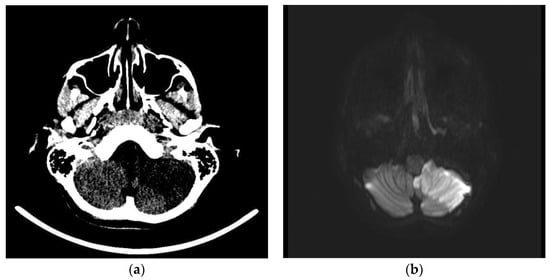

Brain CT scans, performed in 11 patients (9%), revealed alterations in two (1.6%). In the first case, a 12-year-old boy with headache, dizziness, diplopia, and ataxia, it revealed an extensive hypodensity of the left cerebellum and some hypodense spots in the thalami (Figure 2a); in the second one, a 10-month-old infant with MIS-C, with bulging anterior fontanelle and lethargy, it showed cerebral oedema and herniation.

Acute left cerebellar infarct in the distribution of the posterior inferior cerebellar artery (PICA) without mass effect and enhancement areas. Axial brain CT scan (a) and axial brain MRI images of DWI (b), ADC (c), and T1- WI after intravenous gadolinium contrast administration (d) sequences.

Brain or spinal cord MRI, performed in 12 patients (9.8%), was altered in five (4.1%). In the above-mentioned 12-year-old boy, it showed an ischemic injury of the left cerebellum cortex (Figure 2b–d), and the left posterior inferior cerebellar artery (PICA) was unrecognizable in the angiographic sequences. Multiple thalamic ischemic injuries were found also in a 15-year-old boy with confusion and loss of consciousness. In the patient with GBS, the spinal cord MRI showed contrast enhancement of cauda equina roots. In the 10-month-old infant with MIS-C and cerebral oedema on CT, mild cerebral atrophy and areas of altered signal were revealed at MRI performed 2 weeks after the CT scan. In a two-year-old boy with MIS-C and impairment of consciousness, a second MRI, performed after one month from the clinical onset, showed diffuse cortical and subcortical brain atrophy. The three patients with stroke underwent cerebral DSA, which was normal in all but the boy with the cerebellar stroke. The instrumental data are shown in Table 3.

Three patients were diagnosed with AIS during the COVID-19. A 12-year-old boy had a left cerebellar stroke (Figure 2) due to PICA occlusion with a complete clinical recovery but partial radiological improvement. The second was a 15-year-old boy with consciousness impairment and bilateral thalamic ischemic lesions. Despite a clinical improvement, a one-month control brain MRI showed a new cortex ischemic injury. At discharge, his neurological impairments improved with persistent confusion episodes. The third was a six-year-old girl who presented a right central retinal artery occlusion (CRAO) together with an idiopathic contralateral optic neuropathy (Figure 3). Neuroimaging (brain CT, MRI, and angiography) was normal. She completely lost her right eye function, but she recovered her fingers counting on the left.